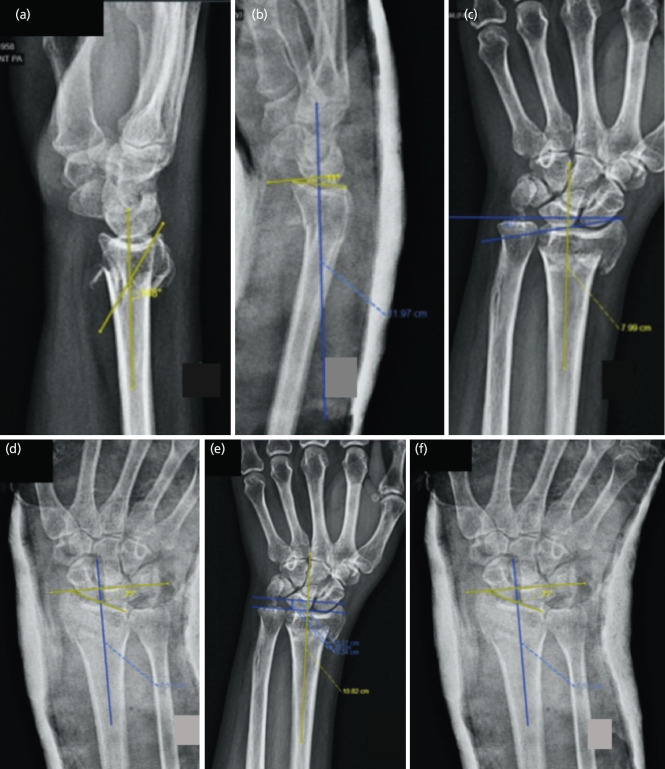

Introduction: Ultrasound-guided manipulation and reduction (M&R) of the distal radius fractures (DRF) is believed to improve radiographic indices due to real-time feedback of fracture alignment. The objective of this trial was to compare volar tilt, radial inclination, and radial height on radiographs between Ultrasound guided and conventional (landmark-guided) M&R.

Materials and methods: A total of 79 distal radius extraarticular fractures in adults were randomised to Ultrasound guided and conventional (landmark-guided) M&R. The radiograph parameters described above were compared before and after M&R in both groups.

Results: Except for volar tilt (P=0.05 difference in difference), there was no difference in both the groups on radiograph parameters i.e. radial inclination and radial height. We estimated a reduction in the incidence of malreduction by 49% (Risk ratio 0.51) and an absolute risk reduction of 22% through USG-guided reduction. We evaluated a number needed to treat 4 through USG-directed M&R of DRF to prevent one unacceptable reduction. There were 9 (22%) and 18 (46%) (P=0.70) unacceptable reductions in USG-guided and landmark-guided M&R.

Conclusion: Adding USG guidance to conventional landmark-based closed reduction methods is not beneficial for the accuracy of fracture reduction in Colle's fracture. However, improved volar tilt in sonographic-directed M&R needs further studies to determine the clinical significance.